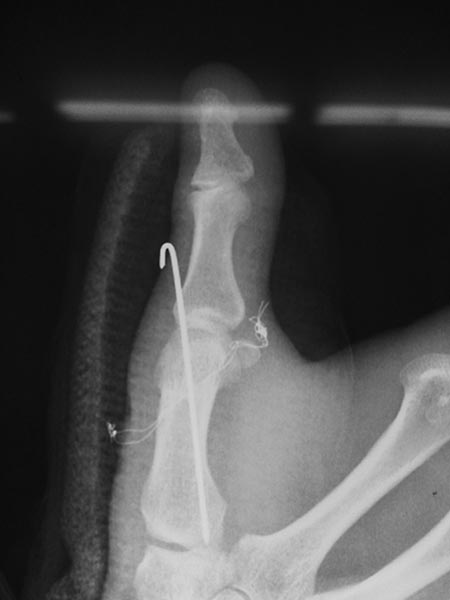

Уважаемые коллеги!!! Помогите разобраться!!! В отделение поступил пациент, которого оперировали в Тайланде 11 ноября 2013г. Травма получена в результате падения с опорой на кисть.

Со слов пациента оперирован по поводу вывиха в пястно-фалангового сустава, вывих закрытый, без повреждения сухожилий (первичных снимков нет). Сделали вот такой остеосинтез (см. фото). Не можем понять для чего проволока??? Пациенту рекомендовали тайландскиие врачи удалить проволоку через 2 месяца со дня операции, проволока выведена на кожу с 2-х сторон.